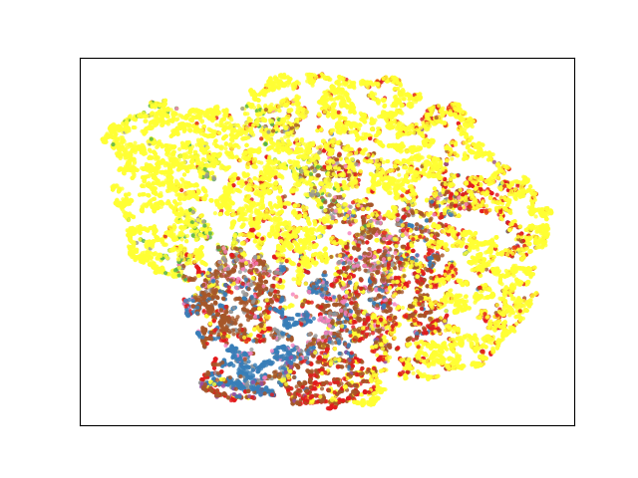

From Table III, we can observe that each major component of our proposed method (i.e., and ) contributes to a more structured representation space in the training process. Specifically, guides unlabeled data to follow the distribution of labeled data, and plays a significant role in generating separated feature representation, as expected.

Recent semi-supervised segmentation approaches in medical imaging have demonstrated promising results by employing various techniques, such as consistency regularization [10, 11], pseudo-labeling [12], and adversarial learning [13]. However, previous methods train the network with the outputs obtained from the final layer, which complicates learning of global features by the network. The proposed method is effective for learning both local and global contexts by embedding voxel-level features with voxel-level feature layers and voxel-level feature discriminators (Table I and Fig. 5). We achieved a more structured representation space (Fig. 7 b) by defining voxel-level feature (including global and local context) relations in the representation space. On comparison with a previous method [13] which also included global contextual information with the discriminator and SDM, our method achieved superior results (Table II), particularly for multiclass datasets. By learning class-specific voxel-level features using BYOL[15] and a multitask discriminator, we achieved a more structured representation space (Fig. 7 and Table III) and precise segmentation results for the multiclass dataset (Table II and Fig. 6). This indicates that our method is effective for learning feature relations across different classes. Moreover, as presented in Table IV, significant performance improvements can be observed for simultaneous use of the voxel-wise feature discriminator and voxel-wise representation learning; this implies that the unlabeled data distribution follows the labeled data distribution as we intended (Table III), thereby embedding rich feature representation. In future studies, we can improve the results by suggesting a more efficient method to enable unlabeled data to follow the distribution of labeled data.